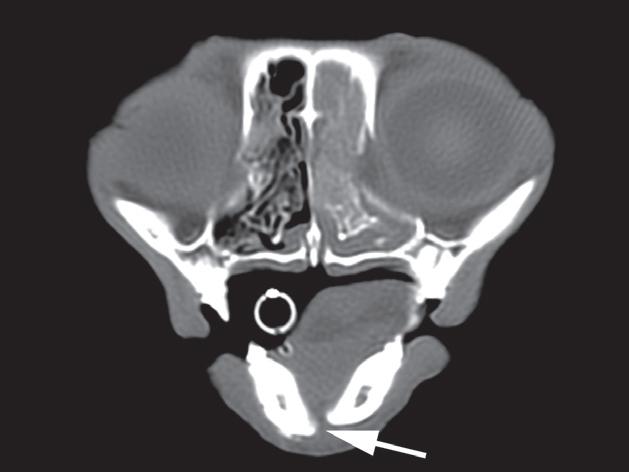

d) TK, TP

e) TK, TP

Badanie wykonano u 5-letniego, kastrowanego kota rasy europejskiej po urazie o nieznanej przyczynie, do którego doszło w ciągu 48 godzin poprzedzających badanie. U kota stwierdzono liczne złamania czaszki typowe dla urazów o dużej sile. Prezentowane obrazy ułożono w kolejności od donosowej do doogonowej. Urazy obejmują: złamanie lub zwichnięcie w obrębie kości nosowych i szczękowych (a – strzałka), separacje spojenia żuchwy (b – strzałka), złamania wyrostków pionowych kości podniebiennych (c – strzałki), rozejście spojenia podniebiennego (c – grot strzałki), złamania kości skrzydłowych (d – strzałki), doogonowe zwichnięcie prawego wyrostka kłykciowego (e – grot strzałki) oraz złamanie przez wyrostek jarzmowy lewej kości skroniowej (e – strzałka)